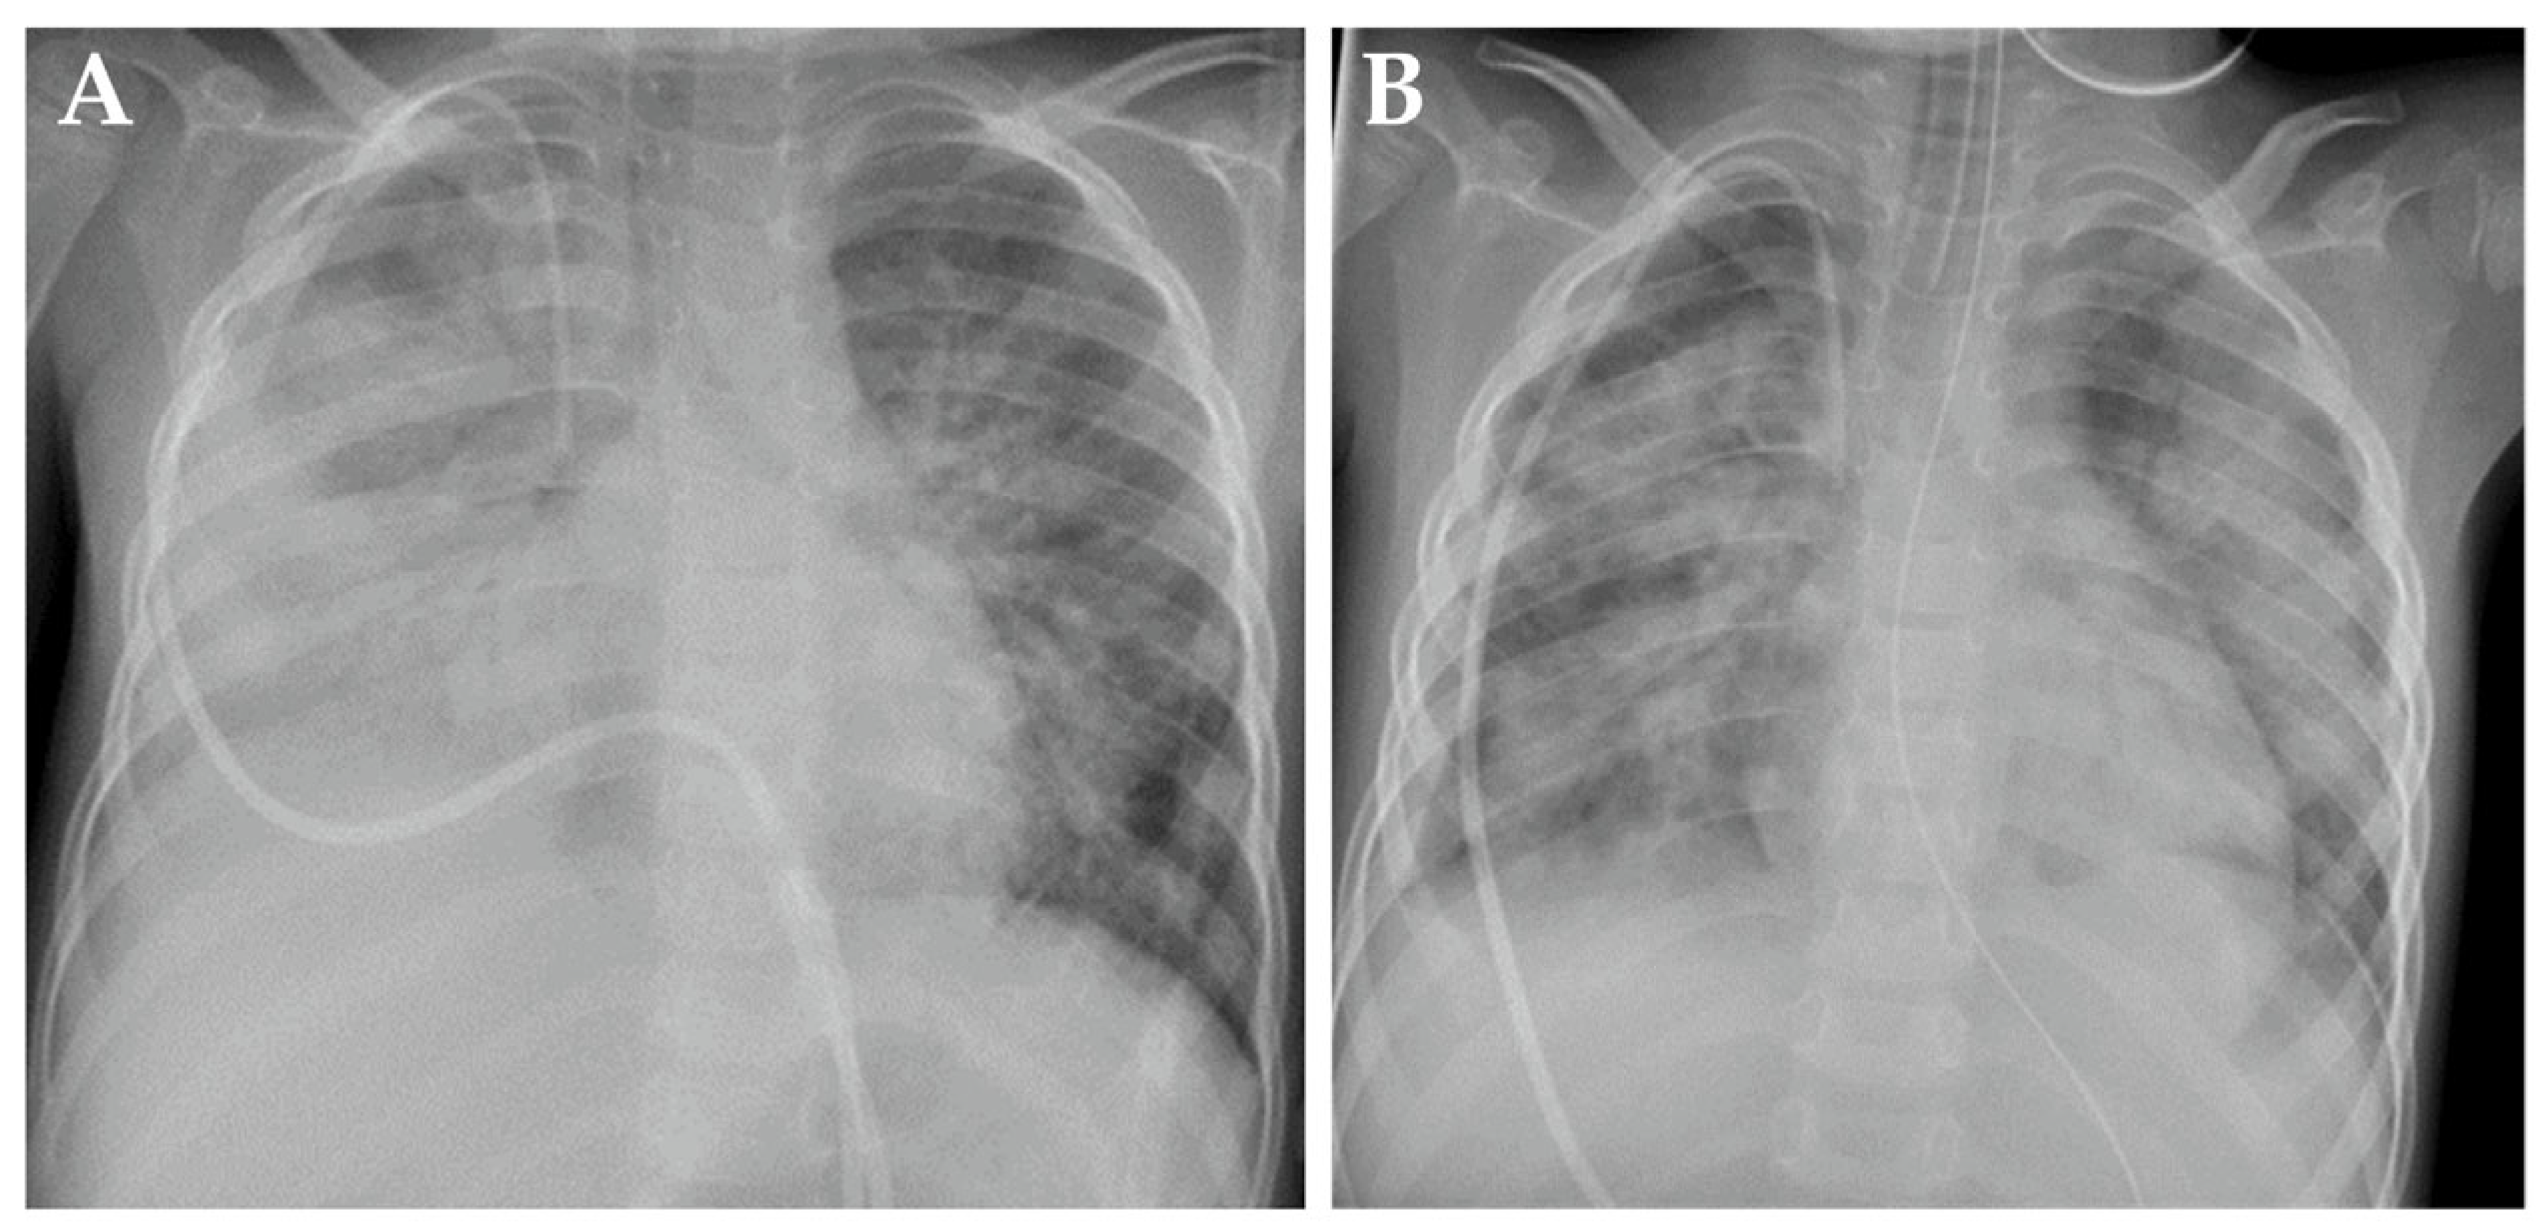

On day 62+, patient 1 developed rapid respiratory deterioration, requiring intubation and invasive mechanical ventilation (IMV) with 100% oxygen and 20 ppm nitric oxide, the latter due to refractory hypoxemia. A chest X-ray showed pathological signs compatible with right-sided pleuropneumonia and overall pulmonary edema (Figure 2A). Immunotherapy was halted. No pathogens were identified in bronchoalveolar lavage, respiratory swabs, blood, urine or stool samples. Broad empirical antibiotic and antifungal therapy was administered immediately after the collection of biospecimens for infectious disease work-up. Assuming a pulmonary cytokine-release syndrome, anti-interleukin 6 therapy with tocilizumab was administered without clear positive effect. After 5 days of IMV and intravenous hydrocortisone (100 mg/m2/d), patient 1 was extubated and continued with non-invasive high-flow nasal cannula therapy.

Figure 2.

Chest X-rays from patient 1 demonstrating signs of busulfan-induced lung injury on day +62 (A) and day +74 (B) after high-dose chemotherapy.

On day +74, respiratory failure with rapidly evolving tachydyspnoea recurred. The chest X-ray now demonstrated bilateral pulmonary infiltrates and pleural effusions (Figure 2B). Patient 1 was re-intubated and placed on IMV as an emergency measure for 6 days. Systemic inflammatory parameters were again high but without a causal pathogen (extensive testing). Empiric antibiotic and antifungal regimens were nevertheless applied. High-resolution computed tomography (HRCT) showed increased ground-glass opacification and consolidation, particularly in both lower lobes (Figure 3A). Busulfan-induced lung injury was the leading differential diagnosis at this stage, and a methylprednisolone pulse was administered (Figure 1). This anti-inflammatory therapy improved the respiratory situation, eventually enabling successful extubation. Patient 1 required non-invasive ventilation followed by high-flow nasal cannula therapy and continuous oxygen supplementation via a nasal cannula for 20 months (Figure 1).